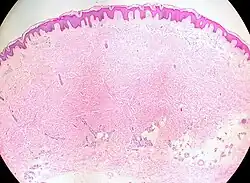

A hematoxylin and eosin-stained sample of the papule or nodule can be examined under a microscope to diagnose cutaneous leiomyomas.[18]

All cutaneous leiomyomas typically exhibit interlacing fascicles of spindle cells with considerable levels of eosinophilic cytoplasm and a blunt-ended, elongated, cigar-shaped nucleus with perinuclear halos on cross section when stained with hematoxylin and eosin (H&E).[5][1] Commonly used smooth muscle stains like Masson's trichrome, aniline blue, Von-Gieson, and phosphotungstic acid hematoxylin (PTAH) are positive for smooth muscle markers like actin and desmin.[4]